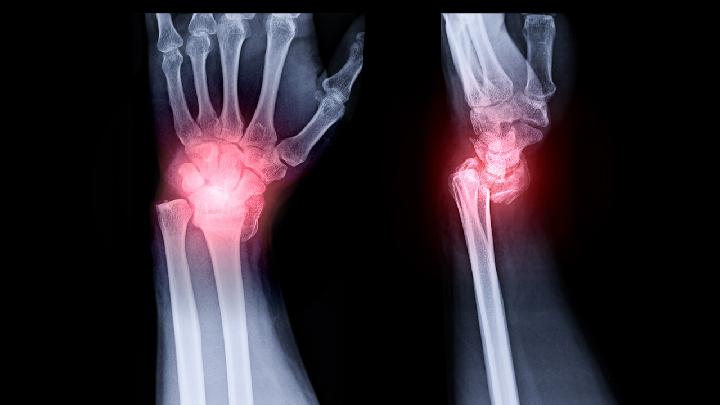

对于此疾病的治疗是可以做按摩治疗的,但主要是对于周围肌肉和下肢的按摩,对于腰椎就不要长期按摩了。而且建议按摩之前先做一些检查,了解一下椎管狭窄的严重程度,在手法上要有所注意,这必须由推拿医生操作,如果手法操作不当,则可能会加重病情的,在急性期间不能按摩,椎管狭窄在治疗方面多采用中医内服和推拿方法:推拿治疗腰椎椎管狭窄症治疗手法: